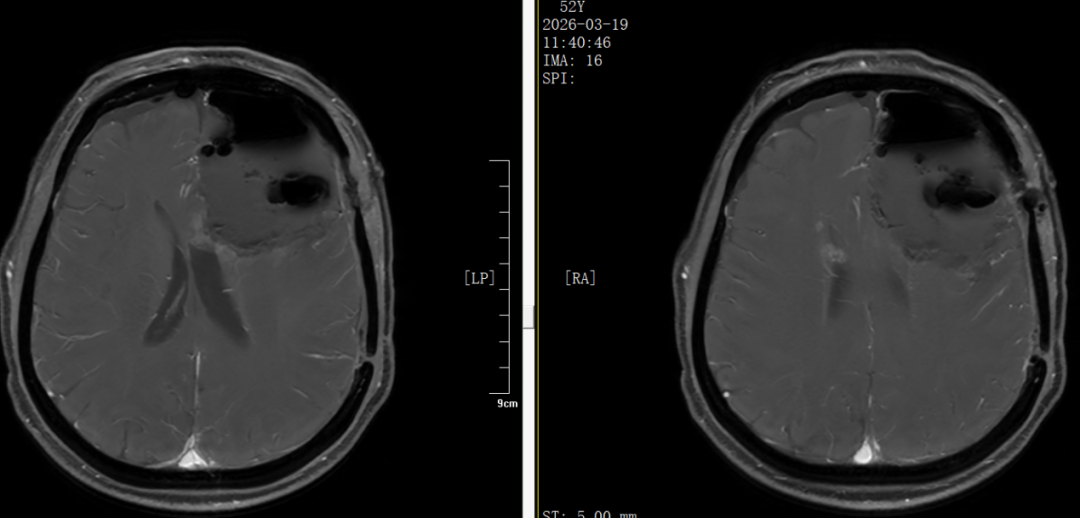

入院后,太阳成集团tyc411(济南)医院神经肿瘤科团队第一时间完善颅脑MRI及血常规、肝肾功能、电解质等检查,全面评估患者病情与身体状况。结果显示:左侧额叶病变较大,占位效应明显,若不及时干预,将进一步压迫脑组织,引发更严重的神经功能障碍,甚至危及生命。

左额叶巨大占位并侵犯胼胝体,中线移位明显,对侧出现小转移灶